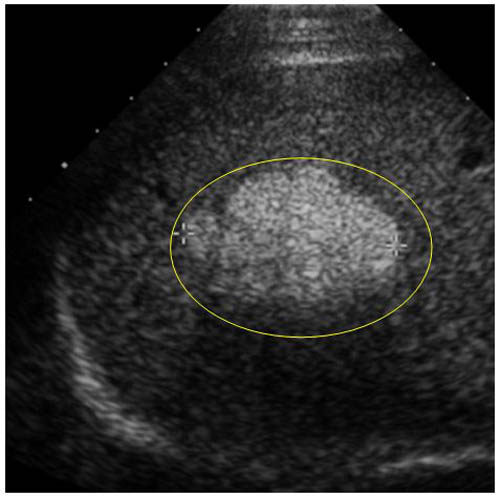

.Siêu âm là 1 xét nghiệm chẩn đoán ung thư gan thông thường nhất được sử dụng để phát hiện ung thư gan. Độ nhạy cảm của xét nghiệm này là 68%-87% (tức là hễ 100 người có khối u trong gan được siêu âm thì có 68-87 người được phát hiện) .thông qua siêu âm gan chúng ta hoàn toàn có thể đánh giá được mức độ tổn thương cấu trúc bề mặt gan.

Một người bị ung thư khi siêu âm gan sẽ thấy gan to toàn bộ hoặc riêng 1 thùy hay phân thùy, mặt gan gồ ghề nếu u nằm ở lớp nông, góc dưới và góc bên của gan mở rộng và tù. Trong trường hợp u bị hoại tử, sẽ thấy hình 1 khối đặc ở giữa rỗng, bờ hốc rỗng dày và không đều.

Ngoài đánh giá về hình dạng, vị trí, số lượng, kích thước khối u gan, siêu âm còn giúp hướng dẫn cho các biện pháp điều trị ung thư gan (cắt gan, tiêm diệt u qua da). Tuy nhiên siêu âm không cho biết bản chất khối u, tình trạng dịch ổ bụng và hạch to. Siêu âm doppler cho phép đánh giá tình trạng cấp máu của khối u, tình trạng khối u xâm lấn và di căn vào các mạch máu lân cận, đặc biệt là tĩnh mạch cửa và tĩnh mạch chủ dưới.